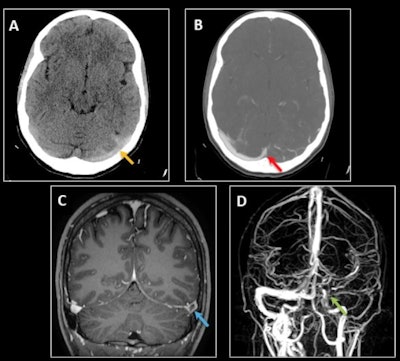

Cerebral venous thrombosis in a 25-year-old woman with a two-week history of left-sided oppressive hemicranial headache and neck pain. (A) Nonenhanced CT shows hyperattenuation of the left transverse and sigmoid sinuses (dense sinus sign) with cortical venous engorgement (yellow arrow). (B) Venous CT angiography shows a filling defect involving the left transverse sinus up to the confluence with the superior sagittal sinus (red arrow), the sigmoid sinus, and the intracranial internal jugular vein. (C-D) MRI sequences confirm a filling defect after gadolinium administration in the left transverse sinus (empty delta sign, blue arrow in C), and the absence of signal on the 3D time-of-flight venous sequence in the left sigmoid and transverse sinuses up to the torcula and in the middle and lower thirds of the superior sagittal sinus (green arrow in D). Factor V Leiden Mutation was disovered. (All images courtesy of Dr. Ana Berasategui Criado et al and presented at ECR 2024).